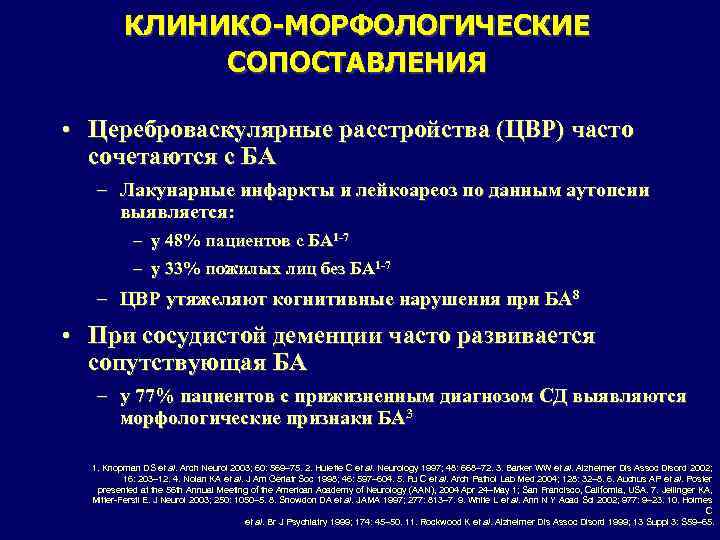

КЛИНИКО-МОРФОЛОГИЧЕСКИЕ СОПОСТАВЛЕНИЯ • Цереброваскулярные расстройства (ЦВР) часто сочетаются с БА – Лакунарные инфаркты и лейкоареоз по данным аутопсии выявляется: – у 48% пациентов с БА 1 -7 – у 33% пожилых лиц без БА 1 -7 – ЦВР утяжеляют когнитивные нарушения при БА 8 • При сосудистой деменции часто развивается сопутствующая БА – у 77% пациентов с прижизненным диагнозом СД выявляются морфологические признаки БА 3 1. Knopman DS et al. Arch Neurol 2003; 60: 569– 75. 2. Hulette C et al. Neurology 1997; 48: 668– 72. 3. Barker WW et al. Alzheimer Dis Assoc Disord 2002; 16: 203– 12. 4. Nolan KA et al. J Am Geriatr Soc 1998; 46: 597– 604. 5. Fu C et al. Arch Pathol Lab Med 2004; 128: 32– 8. 6. Auchus AP et al. Poster presented at the 56 th Annual Meeting of the American Academy of Neurology (AAN), 2004 Apr 24–May 1; San Francisco, California, USA. 7. Jellinger KA, Mitter-Ferstl E. J Neurol 2003; 250: 1050– 5. 8. Snowdon DA et al. JAMA 1997; 277: 813– 7. 9. White L et al. Ann N Y Acad Sci 2002; 977: 9– 23. 10. Holmes C et al. Br J Psychiatry 1999; 174: 45– 50. 11. Rockwood K et al. Alzheimer Dis Assoc Disord 1999; 13 Suppl 3: S 59– 65.